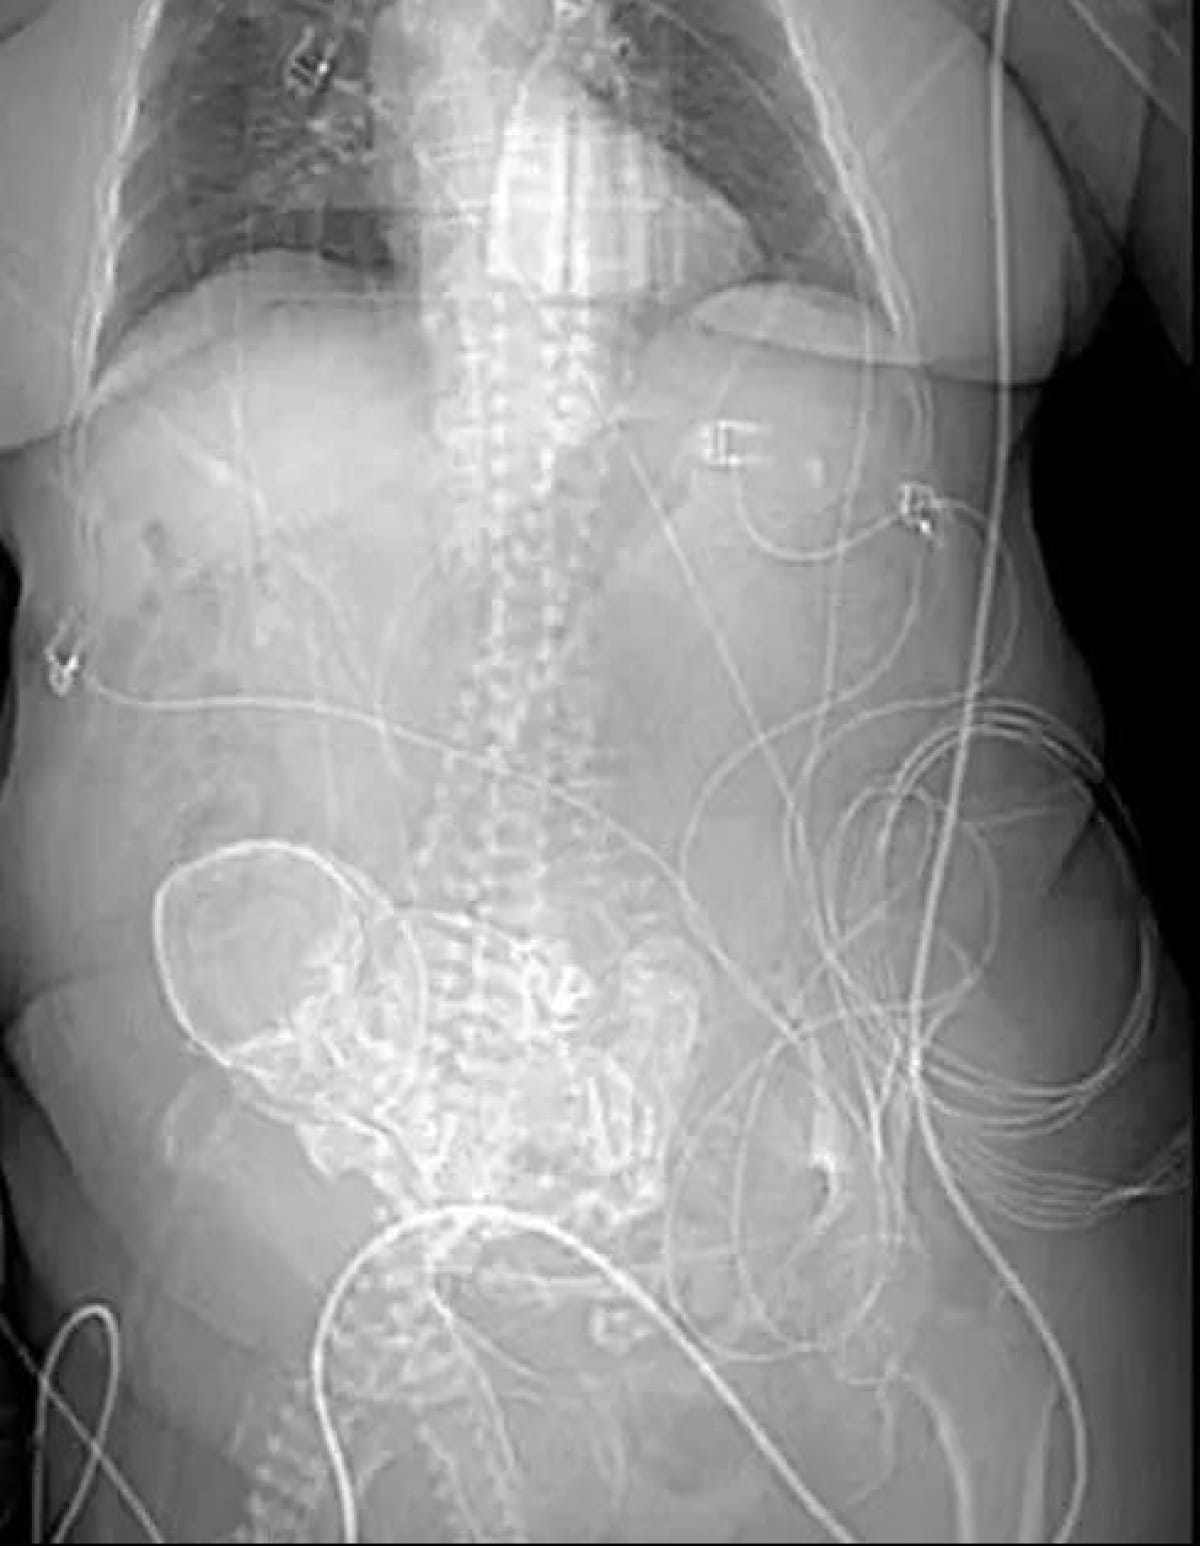

Використовуючи 3D-сканування, лікарі виявили у жінки кальцинований плід, відомий як літопедіон. Спочатку медики припускали, що у пацієнтки може бути ракова пухлина, зважаючи на її скарги на болі в животі. Однак, після обстеження було виявлено скам'янілість, що спонукало до невідкладної операції з її видалення.

На превеликий жаль, хірургічне втручання мало летальний наслідок – жінка померла на наступний день після операції у відділенні інтенсивної терапії.